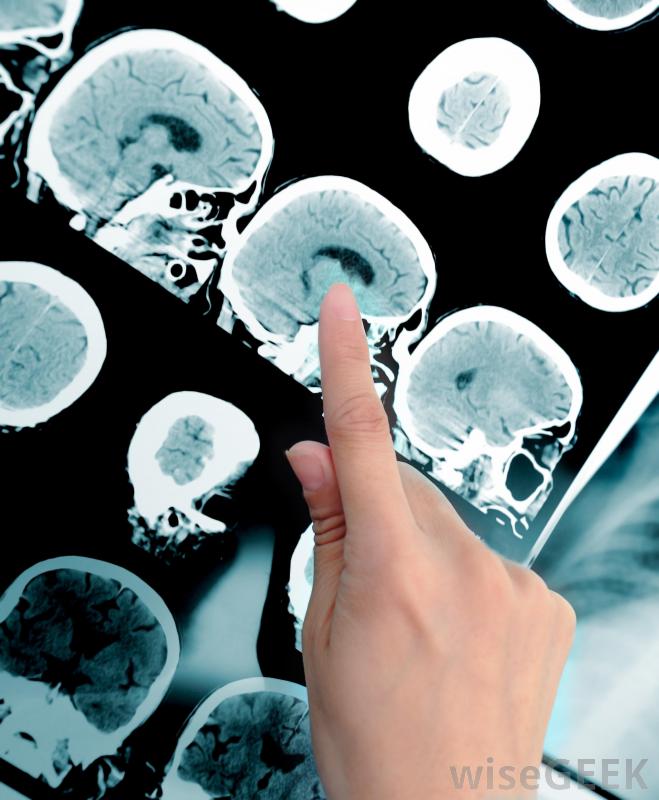

核磁共振技术人员经常从相邻房间观察手术过程。

医疗专业人员使用核磁共振仪诊断内部疾病。